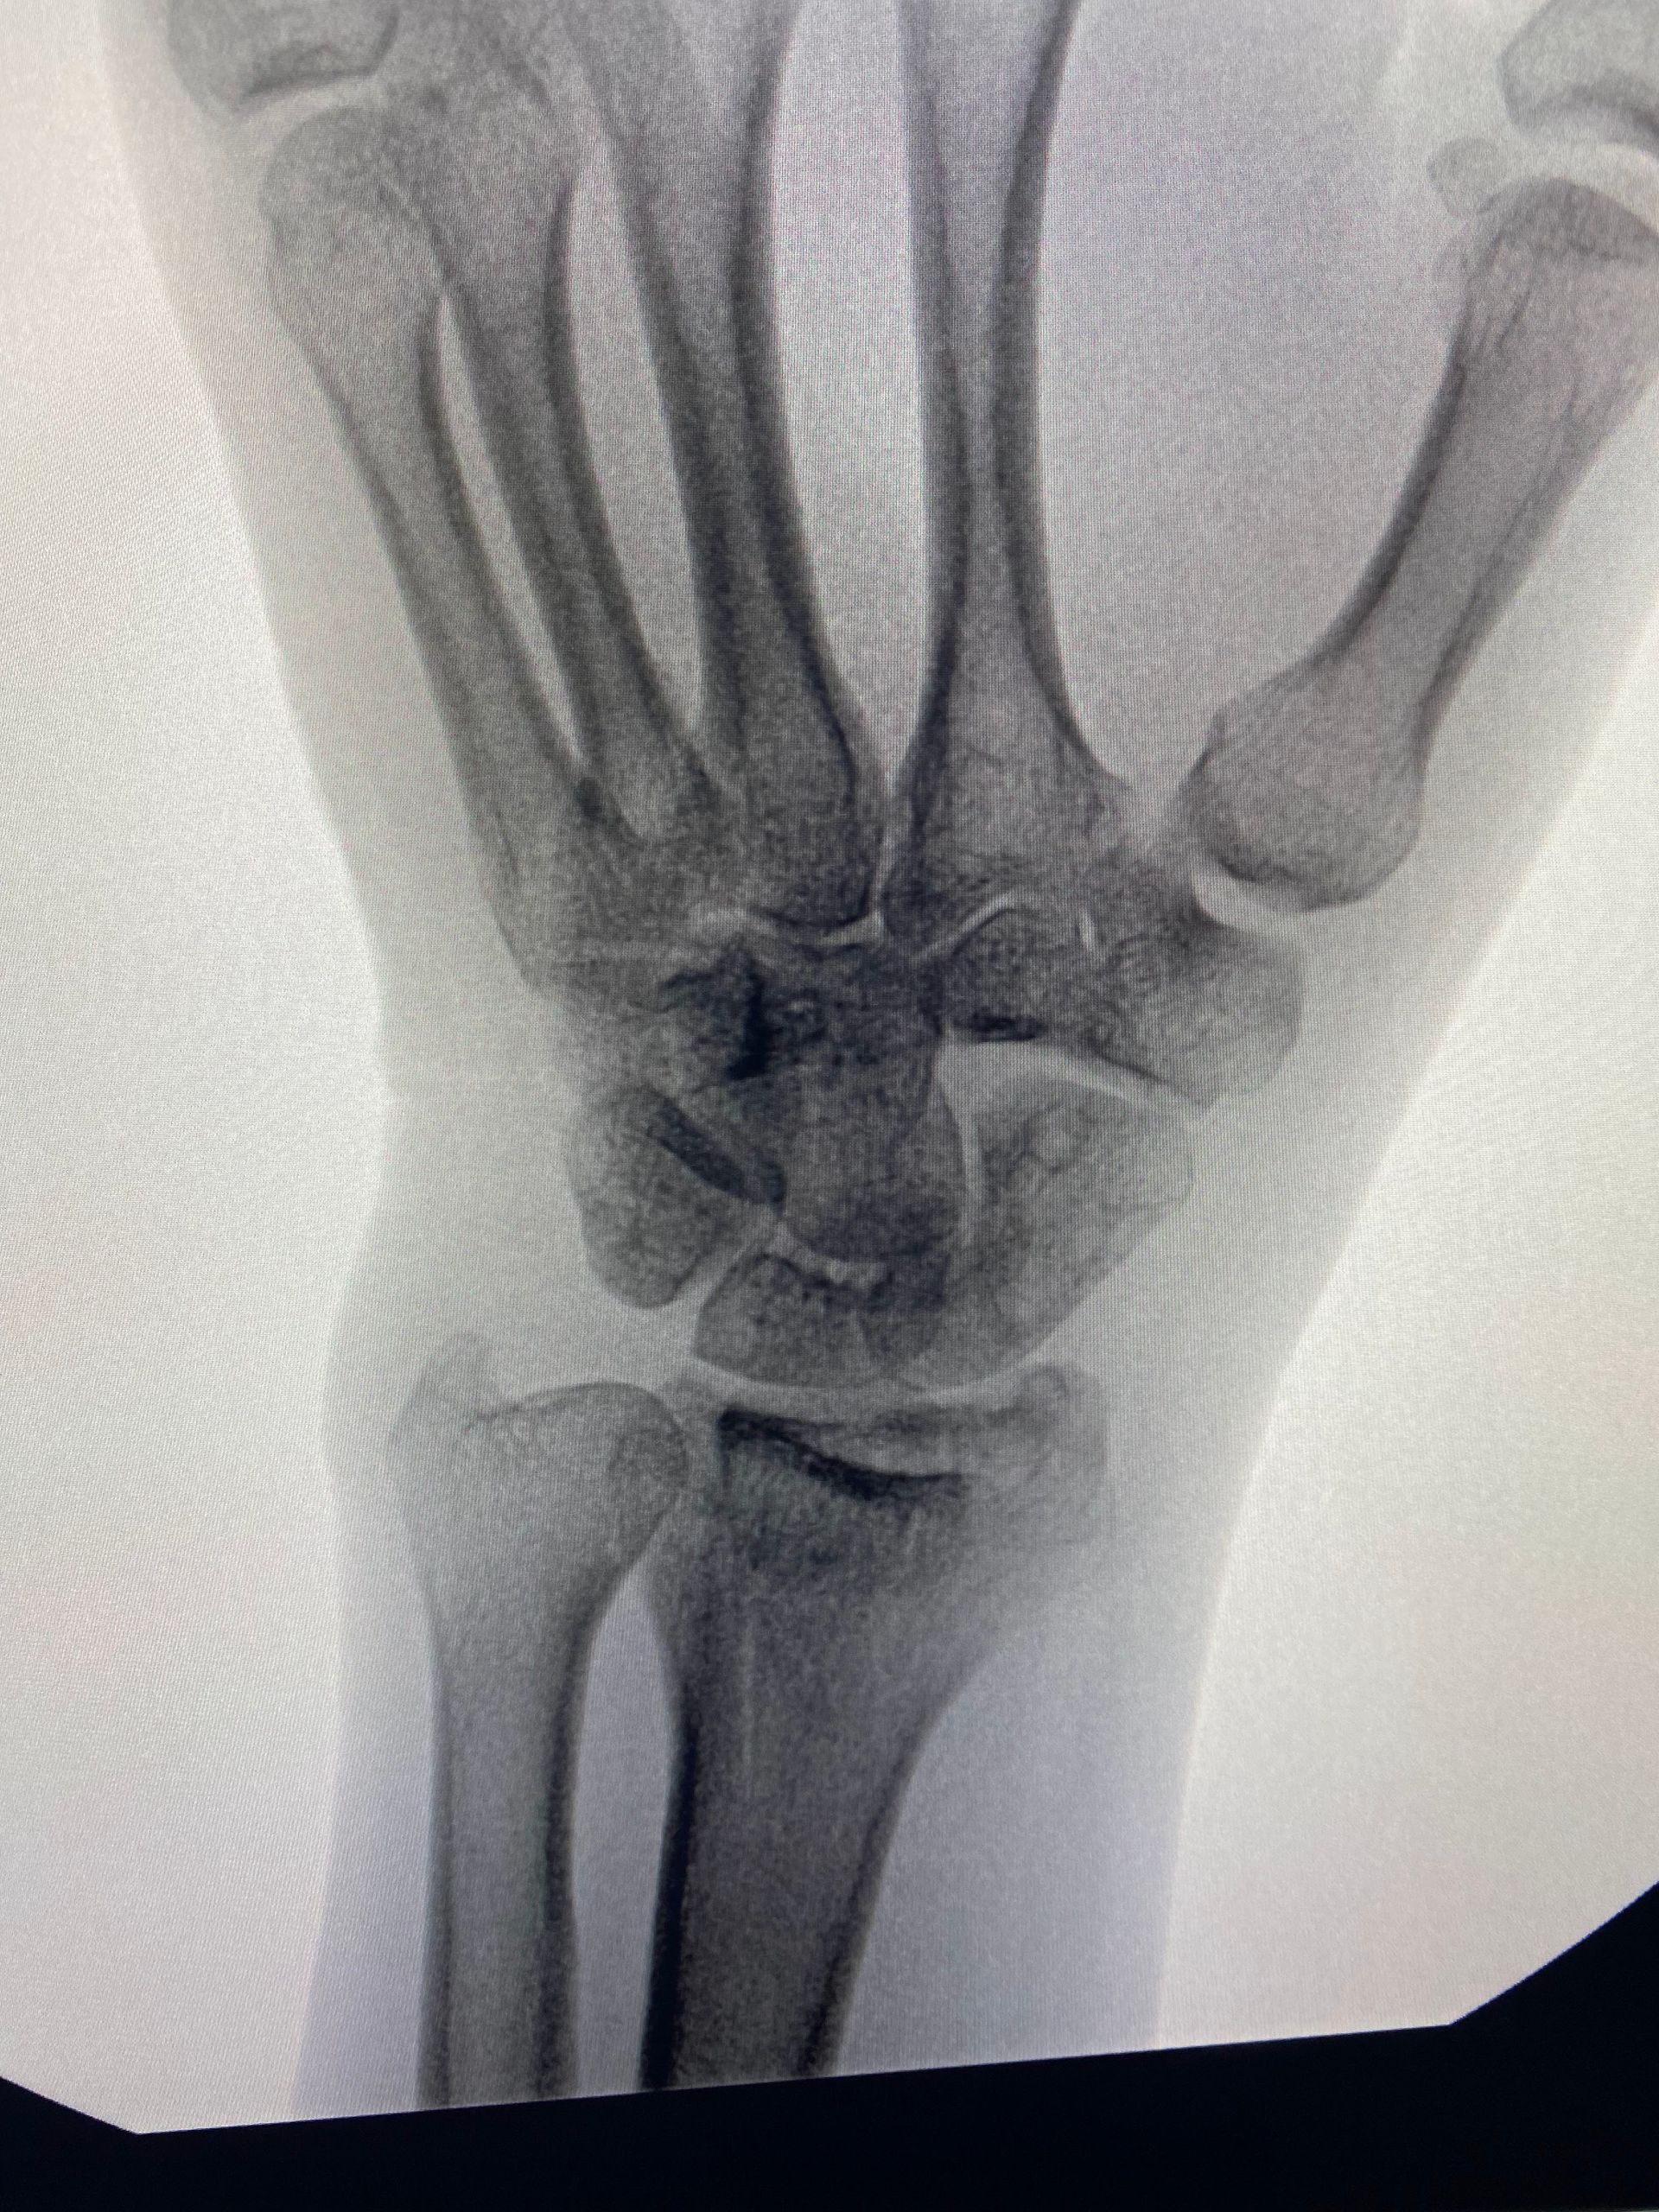

Fernandez tipo III - Fraturas compressivas articulares

- As fraturas tipo "die-punch" são causadas por um trauma axial que causa uma depressão da superfície articular, geralmente na coluna intermediária;

- A redução da fratura de modo preciso está indicada para obtermos resultados ótimos;

- A gravidade da fratura intra articular pode ser difícil de julgar somente pela radiografia, havendo indicação da tomografia computadorizada.

Sequência de imagens na avaliação inicial, radioscopia intra operatória antes da cirurgia, durante a manobra de redução com utilização de um "Freer" e após a fixação da fratura (osteossíntese). A estratégia cirúrgica utilizada envolveu, além da placa e parafusos, o uso de um parafuso canulado introduzido pela borda radial do punho, cuja função foi sustentar o fragmento articular.